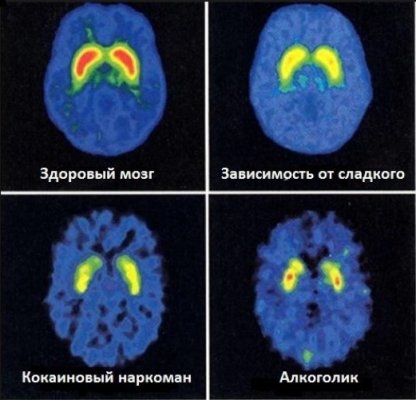

@Анатольевна Можно Вам задать вопрос как патологоанату? Мозги наркомана и здорового человека сильно отличаются? Посмотрела в интернете там в мозгах такой гной. Видна ли энцефалопатия наркоманов?

Чё испугалась? По-любому какся то хрень в мозге осталась. Я когда давно ещё к наркологу ходил, он мне тоже чё то объяснял что там типа как тонкий слой вроде какой то жидкости что-ли, и типа это хрень отмирает. Ну сколько то мозга. Вроде что то так я понял.

Вот гной.